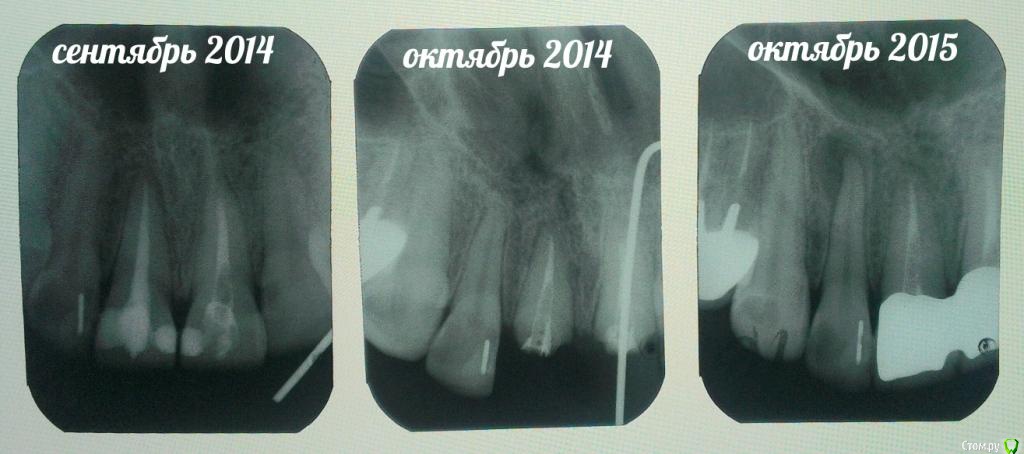

Иноземцева Опубликовано 14 октября, 2015 Поделиться Опубликовано 14 октября, 2015 Добрый день! Год назад откололась передняя двойка. Мне её залечили и поставили парапульпарный штифт. После лечения сделала снимок и врач сказал,что возможно у меня периодонтит (у корня зуба на снимке небольшой ореол), меня ничего не беспокоило.Через какое-то время зуб немного,совсем незаметно потемнел,я думала что это из-за штифта (просвечивает через эмаль зуба). Но через еще какое-то время он заметно поменял цвет. Не могу припомнить,чтобы зуб очень болел, возможно немного поныл и прошел,т.к. дискомфорта я никакого не испытывала.Недавно пошла к стоматологу и предварительно сделала снимок этого зуба и оказалось,что у меня прикорневая киста, причем большого размера,а зуб умер и это послужило причиной изменения цвета.Врач назначил лечение Каласептом. Трепанировал зуб, все прочистил, вложил лекарство и поставил временную пломбу, сказал к нему через месяц. И так в течении года,каждый месяц ставить лекарство,пока не вылечим. После проделанной работы зуб снова стал белым.Сначала зуб не болел,но ближе к вечеру боль усилилась, болит зуб рядом,болит десна у зуба при небольшой надавливании. Боль не острая,а ноющая,ощущение распирания, хочется "почесать" как будто. Утром заметила,что десна припухла и немного осела (на фото видно). Подскажите пожалуйста, как долго можно терпеть такую боль и надо ли ждать месяц до следующего приема или идти раньше?И вопрос по снимкам. Как может возникнуть киста у корня,если зуб был залечен? Это следствие плохого залечивания? У врача спросила, ничего внятного мне не ответил... Заранее огромное спасибо всем откликнувшимся! Ссылка на комментарий